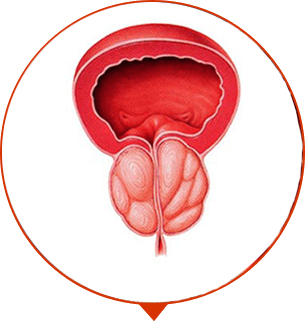

IMPOTENZA

apatia sessuale incurabile

ADENOMA DELLA PROSTATA

Malattia del tessuto della prostata che comporta ammassi tumorali e “nodi”

ONCOLOGIA

Tumore alla prostata, la più comune causa di morte per gli uomini